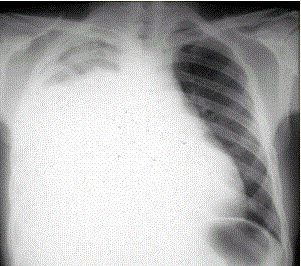

患者男,34岁。进行性胸闷、气促1个月余,伴有干咳、右胸隐痛以及消瘦,无咯血、发热、盗汗、潮热等。(提示 胸部X线检查如图所示)目前的处理措施...

问题 患者男,34岁。进行性胸闷、气促1个月余,伴有干咳、右胸隐痛以及消瘦,无咯血、发热、盗汗、潮热等。 (提示 胸部X线检查如图所示) 目前的处理措施正确的是

选项 A.高流量吸氧 B.给予紧急配血和输血 C.使用糖皮质激素 D.静脉溶栓 E.静脉给予利尿药 F.静脉给予肾上腺素 G.加快胸腔积液的引流 H.静脉给予广谱抗生素 I.紧急外科手术 J.必要时机械通气

答案 ACEJ

解析 ACEJ